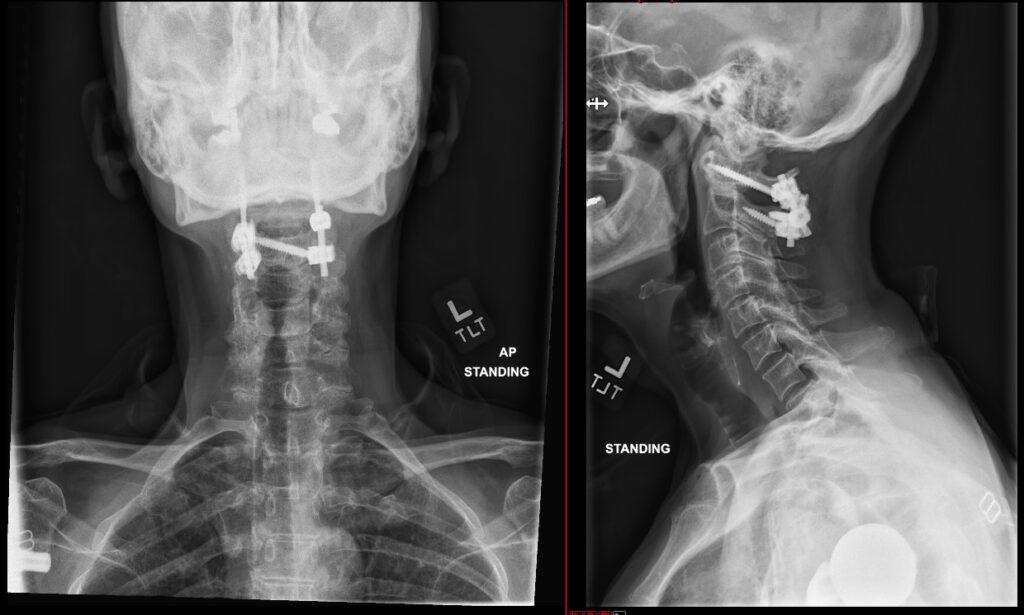

C1-2 fusion